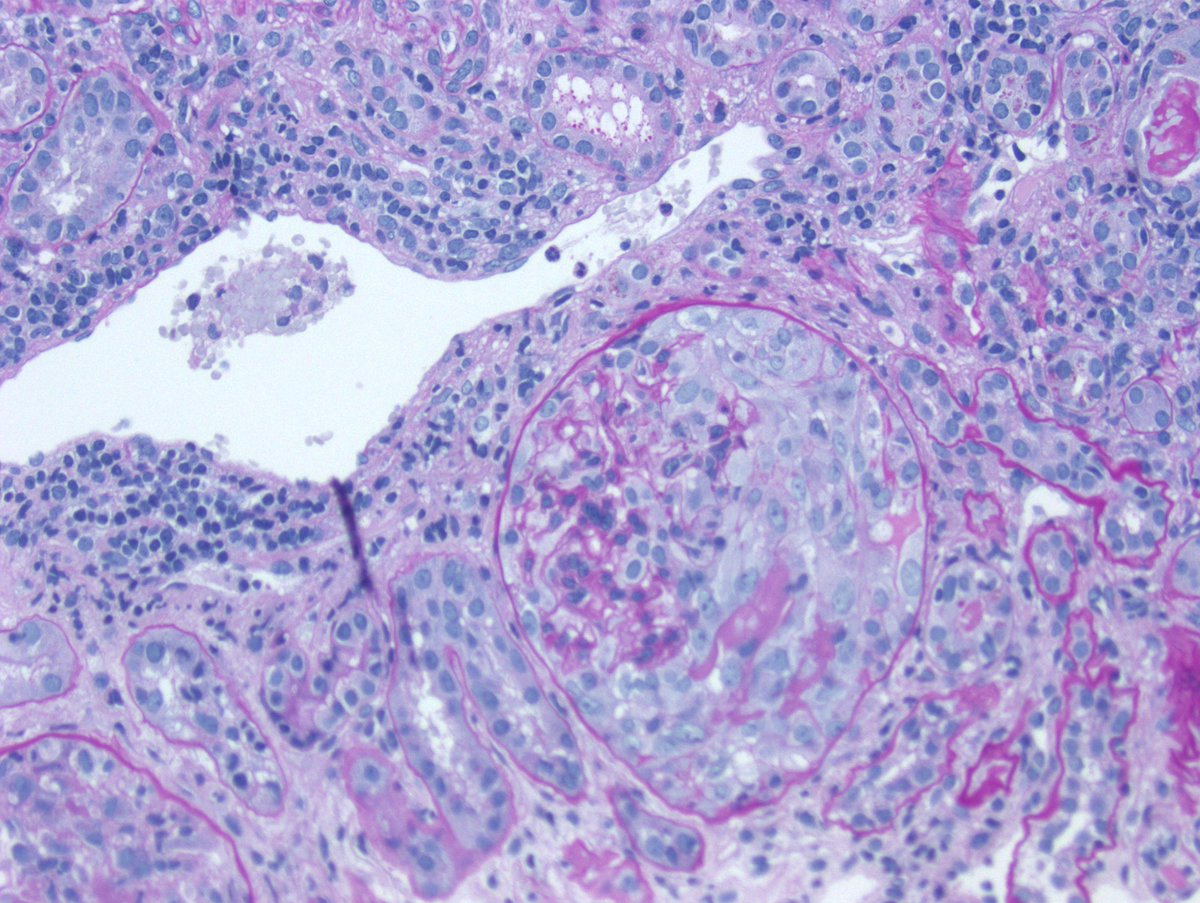

Long weekend often brings urgent cases. Here is one that was STATed, ended up showing anti-GBM GN. Diffuse crescents (nearly 100%). Linear IgG. #RenalPath